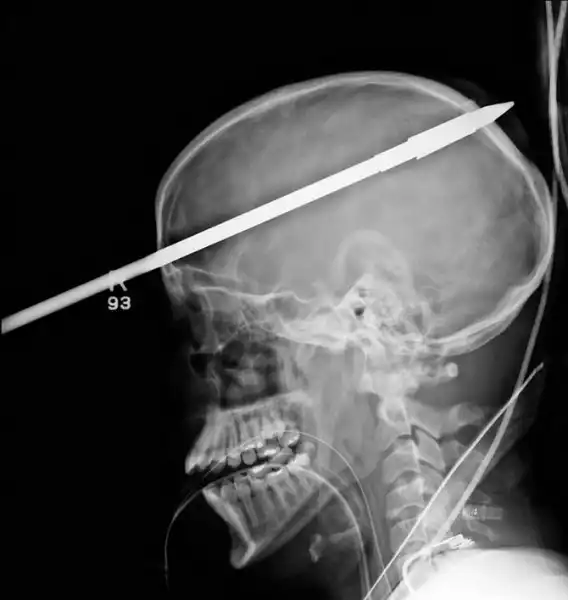

Копье от гарпуна, попавшее в голову 16-летнему мальчику на рыбалке.